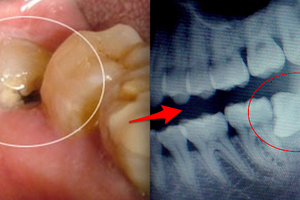

千萬不要再「不拔智齒」了,90%的人全搞錯了!這些人長年沒拔智齒,沒想到口腔最後竟然...太可怕了!